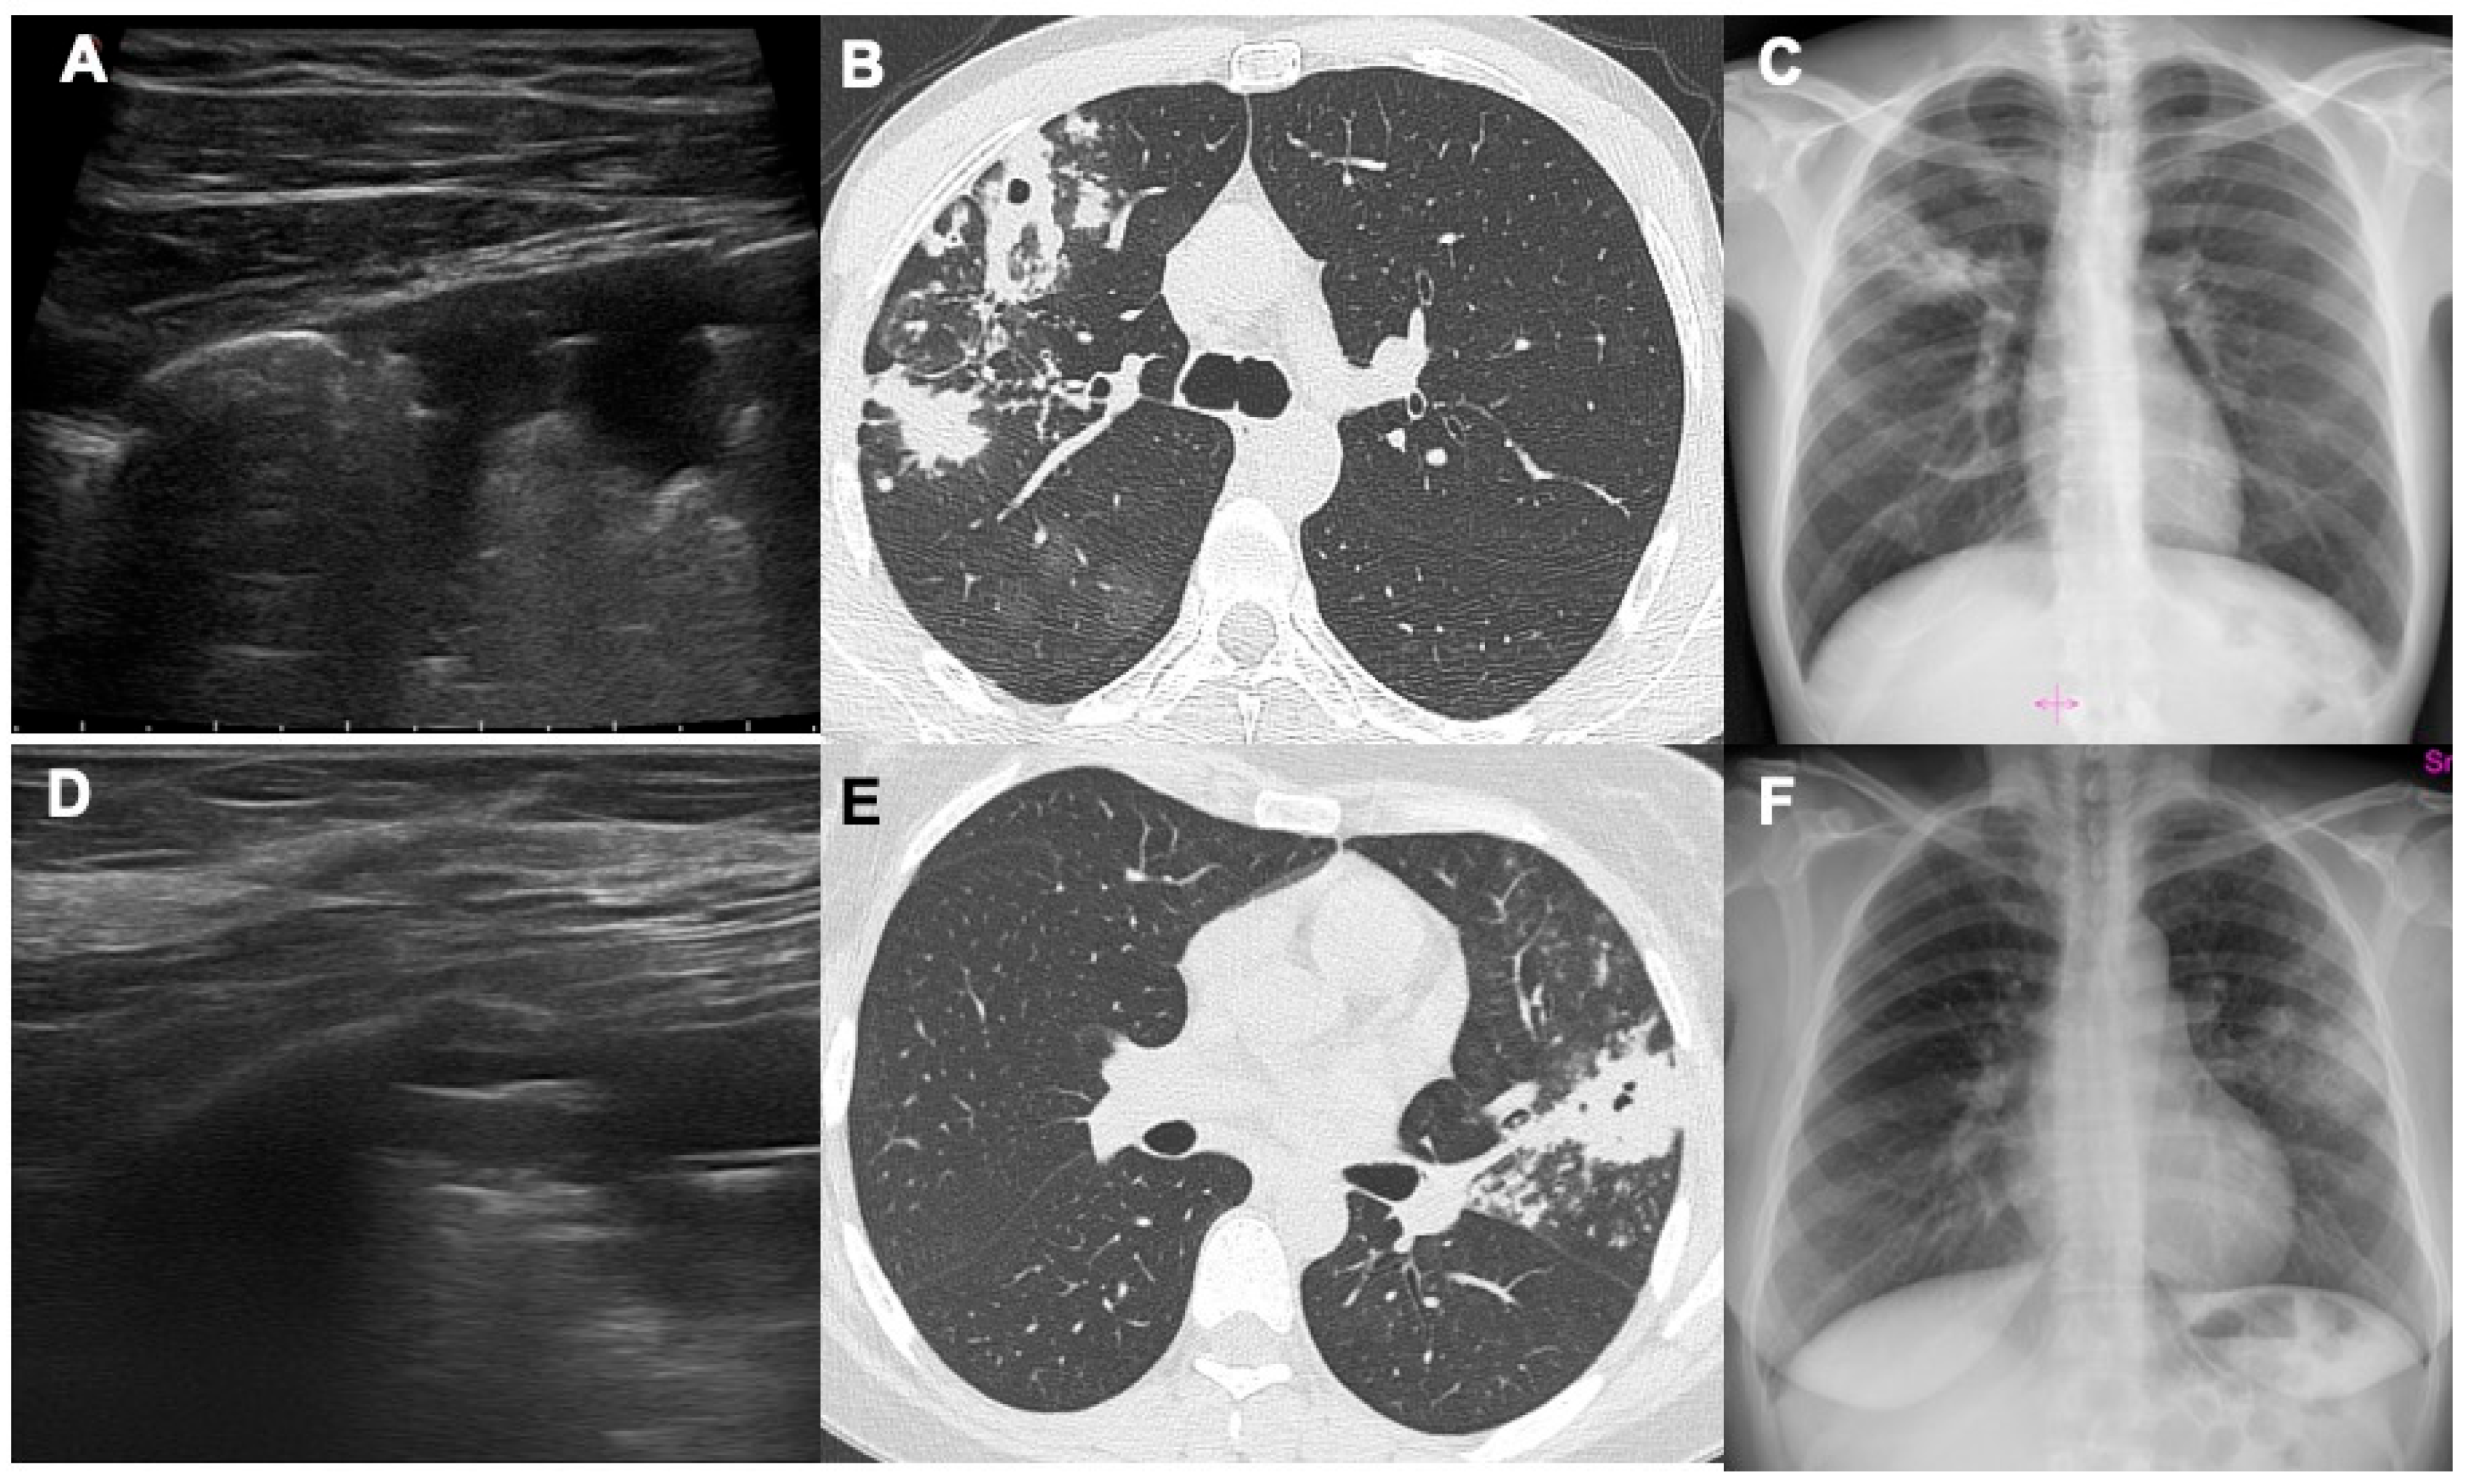

- Giannelli, F.; Cozzi, D.; Cavigli, E.; Campolmi, I.; Rinaldi, F.; Giachè, S.; Rogasi, P.G.; Miele, V.; Bartolucci, M. Lung ultrasound (LUS) in pulmonary tuberculosis: Correlation with chest CT and X-ray findings. J. Ultrasound 2022, 25, 625–634. [Google Scholar] [CrossRef]